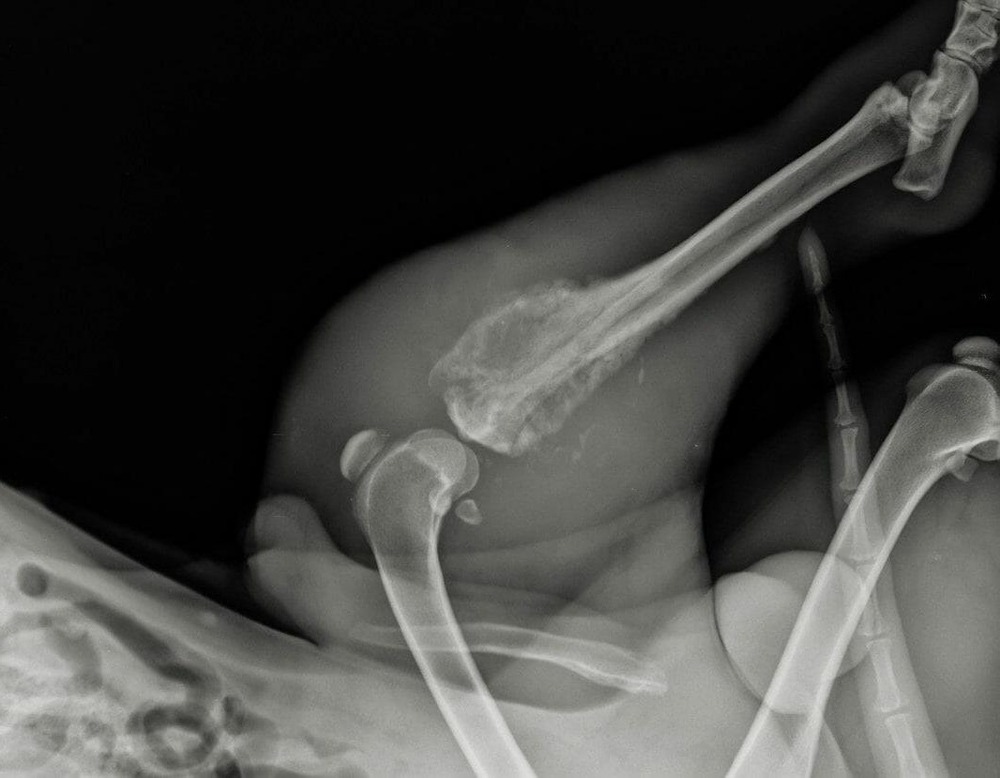

Most work-ups start with a physical exam and orthopaedic x-rays of the affected limb. Radiographs can show patterns of bone destruction and new bone formation that raise strong suspicion for a bone tumour.1